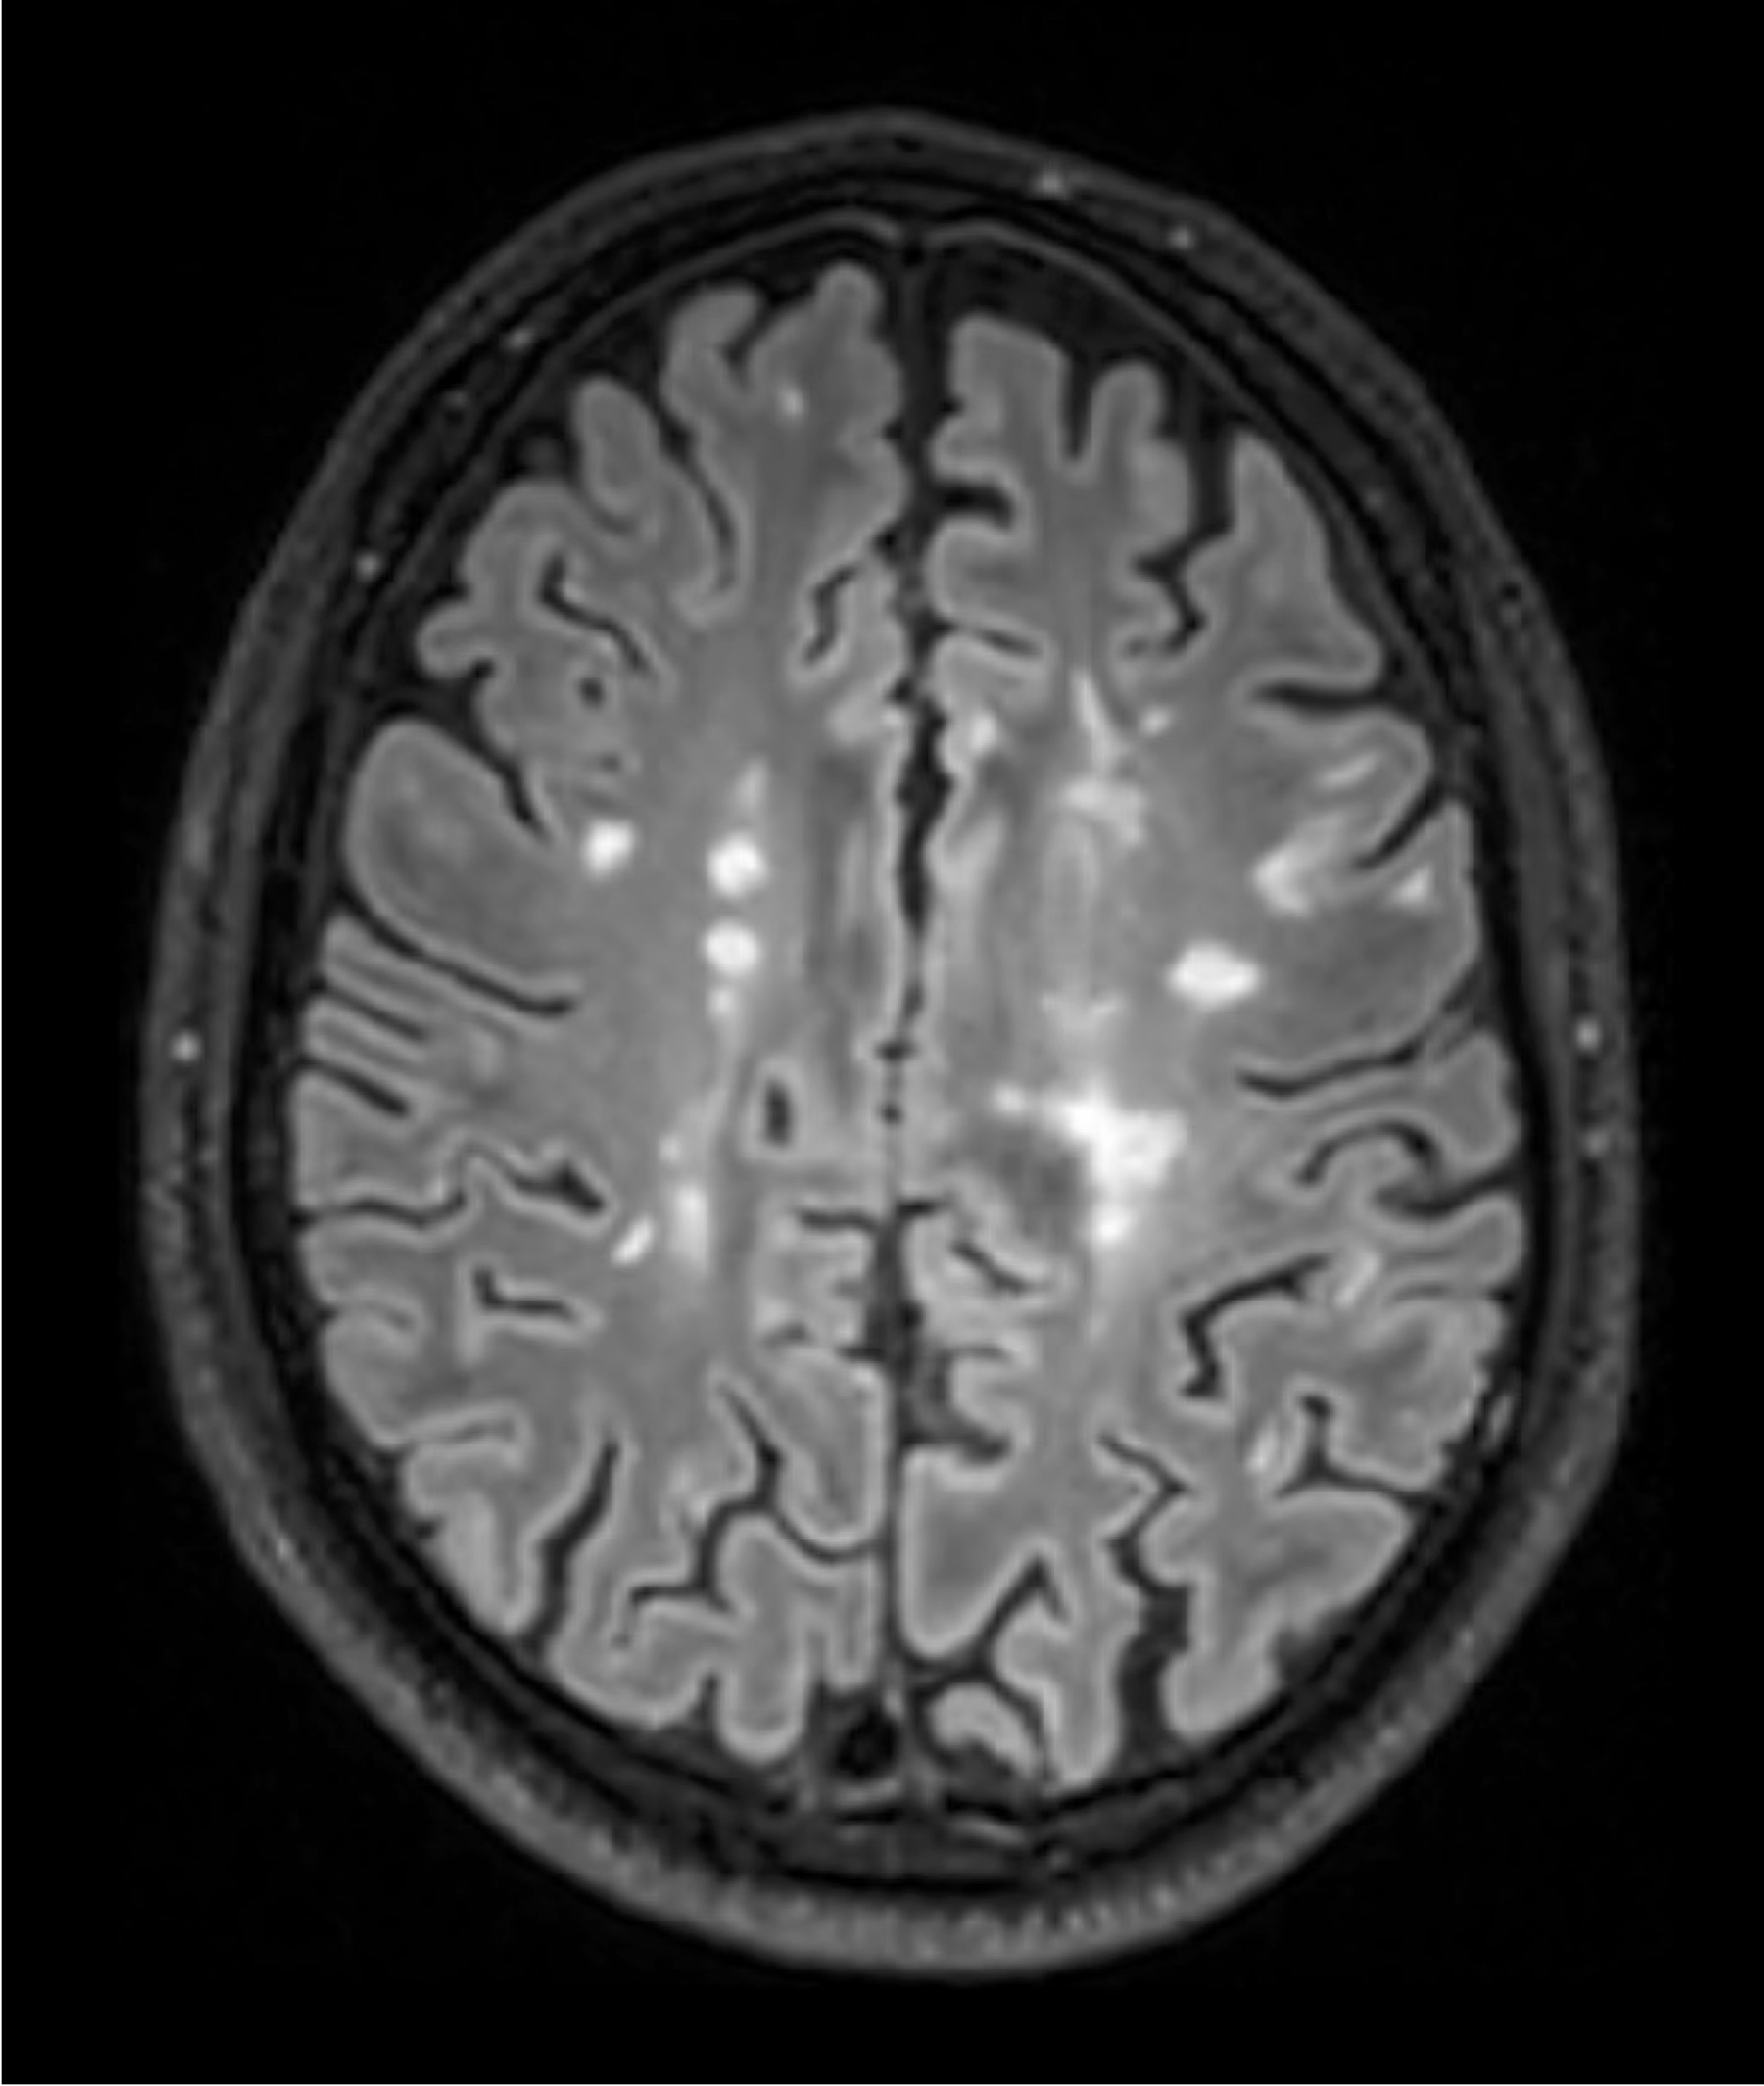

BU: Die Aufnahmen aus der Magnetresonanztomographie zeigen einen jungen Patienten mit Multipler Sklerose mit mehreren entzündlichen Läsionen des Gehirns. (© Radiologie Innsbruck)

Abseits klinischer Symptome, die von Einschränkungen des Sehvermögens bis hin zu Lähmungserscheinungen ein breites Spektrum umfassen, kann die Krankheitsaktivität bei MS auch bildgebend dargestellt werden. „Der Nachweis entzündlicher Läsionen im Gehirn mittels MRTerlaubt auch eine Einschätzung geringerer Krankheitsaktivität, denn vermeintlich stabile Patient:innen können trotz Therapie weiterhin neue, klinisch stumme, entzündliche Veränderungen entwickeln“, weiß Neuroimmunologe Harald Hegen, der an der Innsbrucker Univ.-Klinik für Neurologie bereits seit vielen Jahren zu MS forscht.

In die Studienkohorte wurden 131 MS-Patient:innen aus MS-Zentren in Österreich und der Schweiz eingeschlossen, die unter einer gering- bis moderat-effektiven Immuntherapie zwölf Monate lang klinisch stabil waren und dann einer MRT unterzogen wurden. „Wir konnten zeigen, dass Patient:innen mit schubförmiger MS, die unter Immuntherapie zwei oder mehr neue entzündliche MRT-Läsionen innerhalb eines Jahres entwickeln, auch bei klinischer Stabilität, also ohne Symptome, von einem Wechsel auf eine hoch-effektive Immuntherapie profitieren“, beschreibt Erstautor Gabriel Bsteh von der Medizinischen Universität Wien die zentrale Erkenntnis. Damit liefert die Studie eine für den klinischen Alltag wichtige Erkenntnis, die für die individuelle Therapieanpassung genutzt werden sollte.

„Nachdem Läsionen oft schon vor dem Auftreten klinischer Symptome in der MRT sichtbar sind, ermöglicht eine bildgebende Kontrolle bei Patient:innen mit einer gering- bis moderat-effektiven Therapie ein frühes Eingreifen in den individuellen Krankheitsverlauf“, betont Studienleiter Harald Hegen. In der Studienkohorte waren rund 40 Prozent der Patient:innen klinisch stabil, zeigten allerdings in der MRT schon eine oder mehrere Läsionen. Bislang war in der klinischen Praxis eine Therapieverstärkung nur nach Auftreten klinisch manifester Symptome angezeigt.